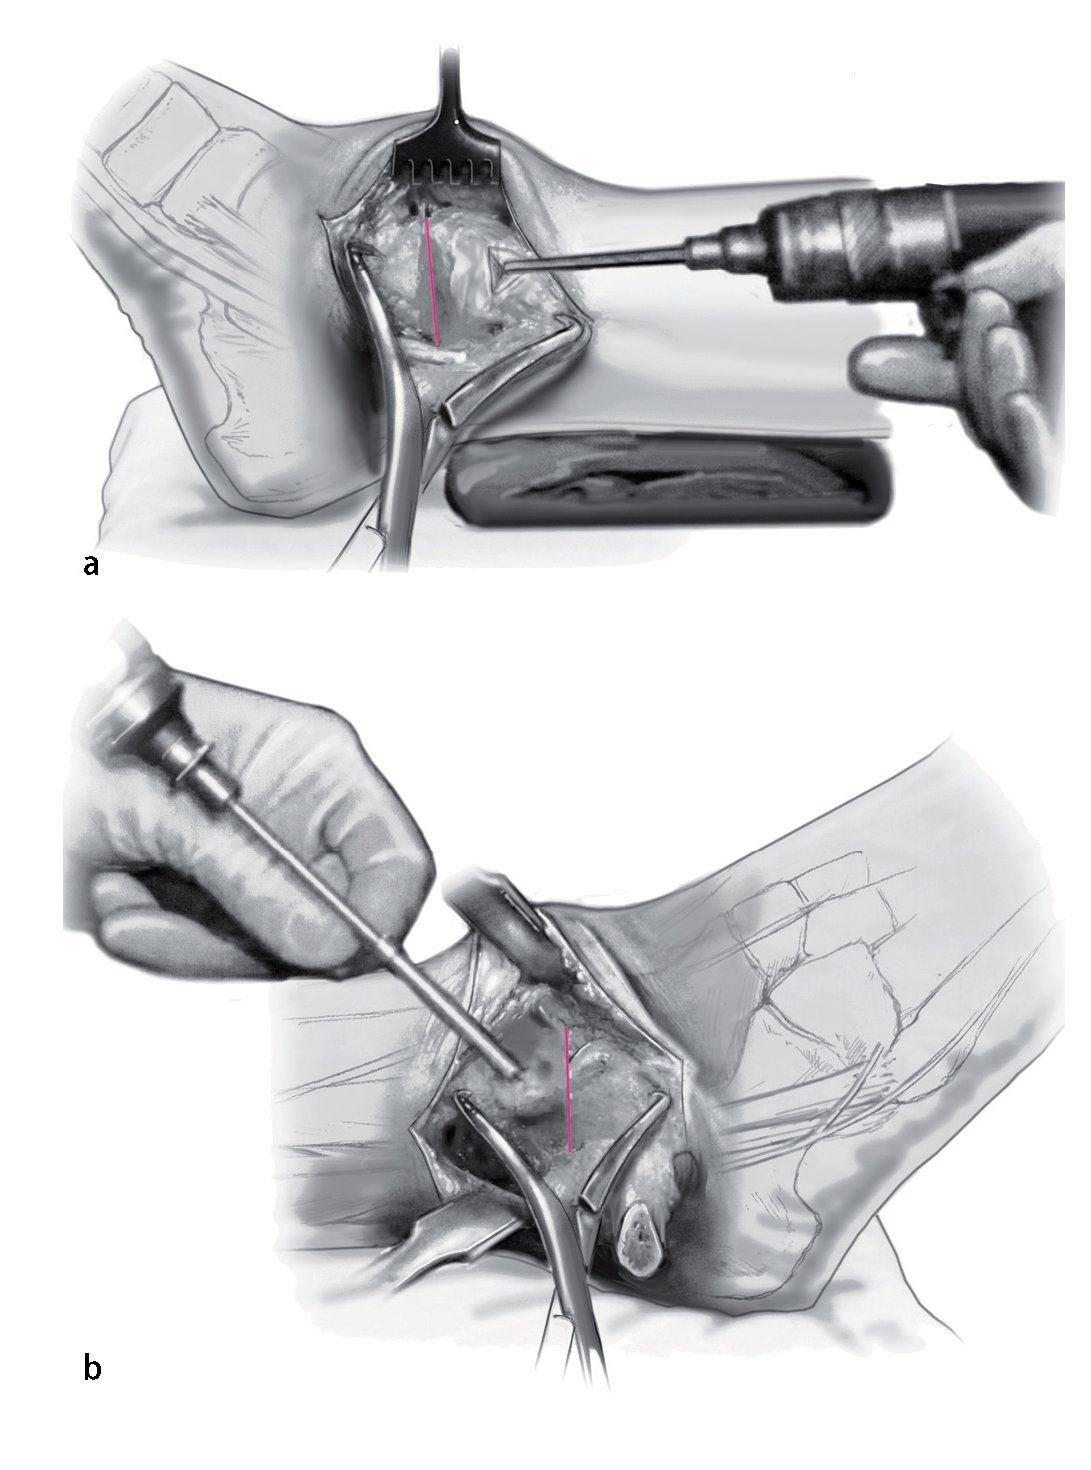

Fig. 3 Aborde el peroné desde un plano lateral en línea recta (a). La cápsula de la articulación se reseca parcialmente para dejar visible la sección tibioastragalina anterolateral (b). Realice una incisión en la vaina de tendón extensor y levante los tejidos blandos de la tibia en una sola capa. Ahora se puede colocar un separador de Hohmann para permitir una mejor visibilidad de toda la sección anterior del tobillo.

Fig. 4 En el ángulo posterolateral se realiza incisión en la vaina tendinosa peronea. Colocar los separadores de Hohmann como protección en posición anterior y posterior del peroné. Realizar osteotomía oblicua del peroné (a) usando la sierra oscilante a unos 6 cm por encima del espacio articular. Se reseca una sección de 8 mm para facilitar la compresión apropiada al final del procedimiento. Gire el peroné en dirección dorsocaudal (b).

Fig. 5 Decortización de la cara medial del peroné distal con sierra oscilante. Esto aumenta la potencia biológica de la refijación.